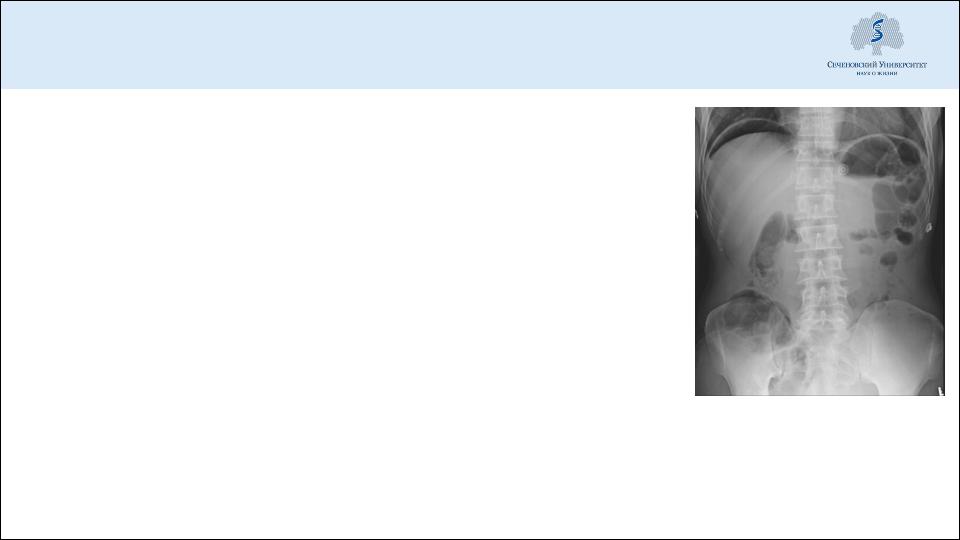

Отсутствие печеночной тупости при перкуссии

Свободный газ в брюшной полости при рентгенографии

УЗИ – большое количество жидкости в брюшной полости, при диагностической аспирации примесь желчи